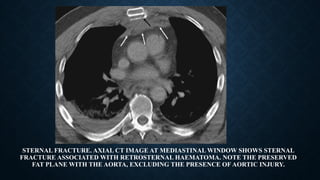

STERNUM FRACTURE

• Sternal fractures: 3–8% in blunt chest trauma.

• Main mechanism: deceleration injury/direct blow to the anterior chest wall.

• Difficult to detect on lateral chest radiographs .

• Almost always accompanied by anterior mediastinal haemorrhage, which has a preserved fat

plane with the aorta, as opposed to an anterior mediastinal haemorrhage secondary to aortic

injury, which will present with a lost fat plane with the aorta.

STERNAL FRACTURE. AXIAL CT IMAGE AT MEDIASTINAL WINDOW SHOWS STERNAL

FRACTURE ASSOCIATED WITH RETROSTERNAL HAEMATOMA. NOTE THE PRESERVED

FAT PLANE WITH THE AORTA, EXCLUDING THE PRESENCE OF AORTIC INJURY.